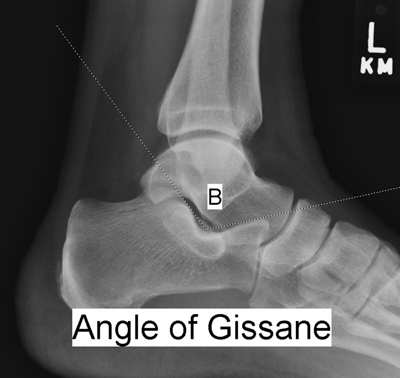

“Crucial angle” of Gissane (Figure 2): On the lateral x-ray, the angle formed by the wedge in which the lateral process of the talus sits; this angle is disrupted when axial compressive forces drive the talus as a wedge into this space. Radiograph of the uninjured side is useful for comparison; may not be as helpful as the Böhler angle in determining the presence of a calcaneus fracture (6).